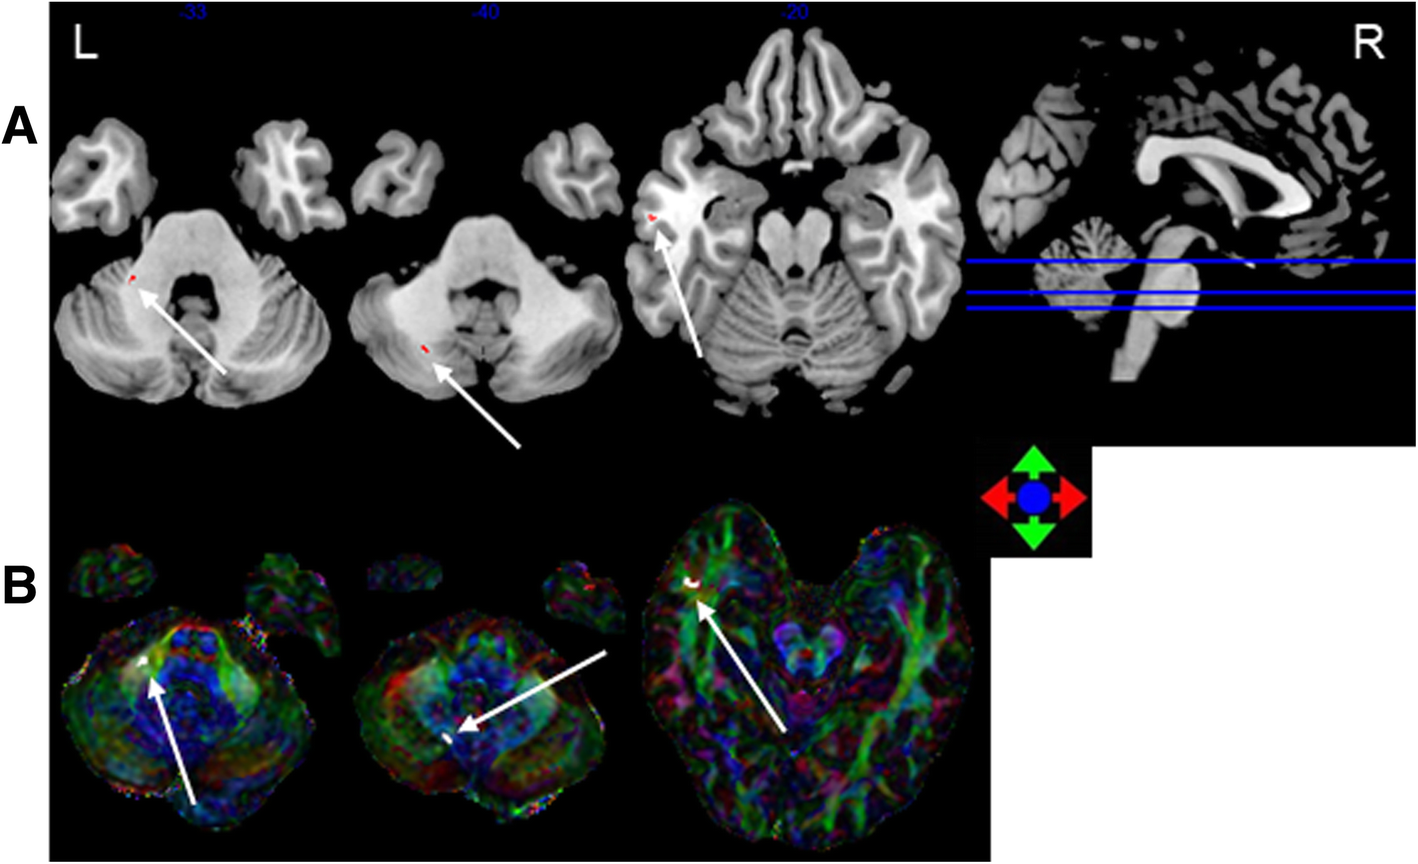

Fig. 2

The most discriminating voxels for the classification of 6–12 months post-RT versus control; the image is the cutaway view: a displayed on the mean group fractional anisotropy (FA) map, the abnormal regions are shown in red; b FA map displayed in color (Red represents the left and right direction, green represents the up and down direction, and blue represents the front and rear direction). The left side of the brain is on the left side of the image. L = left, R = right